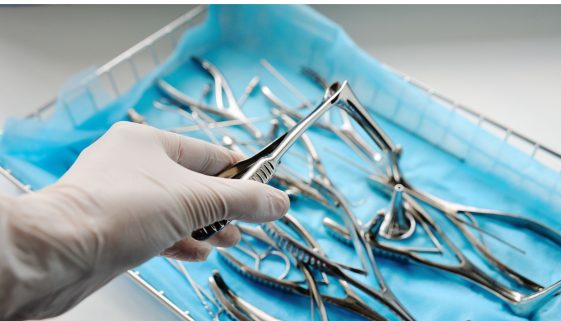

تعد الجراحة العامة للأطفال من المجالات الطبية الحساسة التي تتطلب اهتمامًا خاصًا وعناية فائقة لضمان صحة الأطفال ورفاهيتهم. يتطلب هذا النوع من الجراحة التعامل مع الأطفال بطريقة تراعي احتياجاتهم النفسية والجسدية. الهدف من هذه المقالة هو تقديم نصائح وتعليمات تثقيفية للآباء والأمهات ومقدمي الرعاية للإعداد للجراحة وضمان الشفاء السريع لأطفالهم. […]